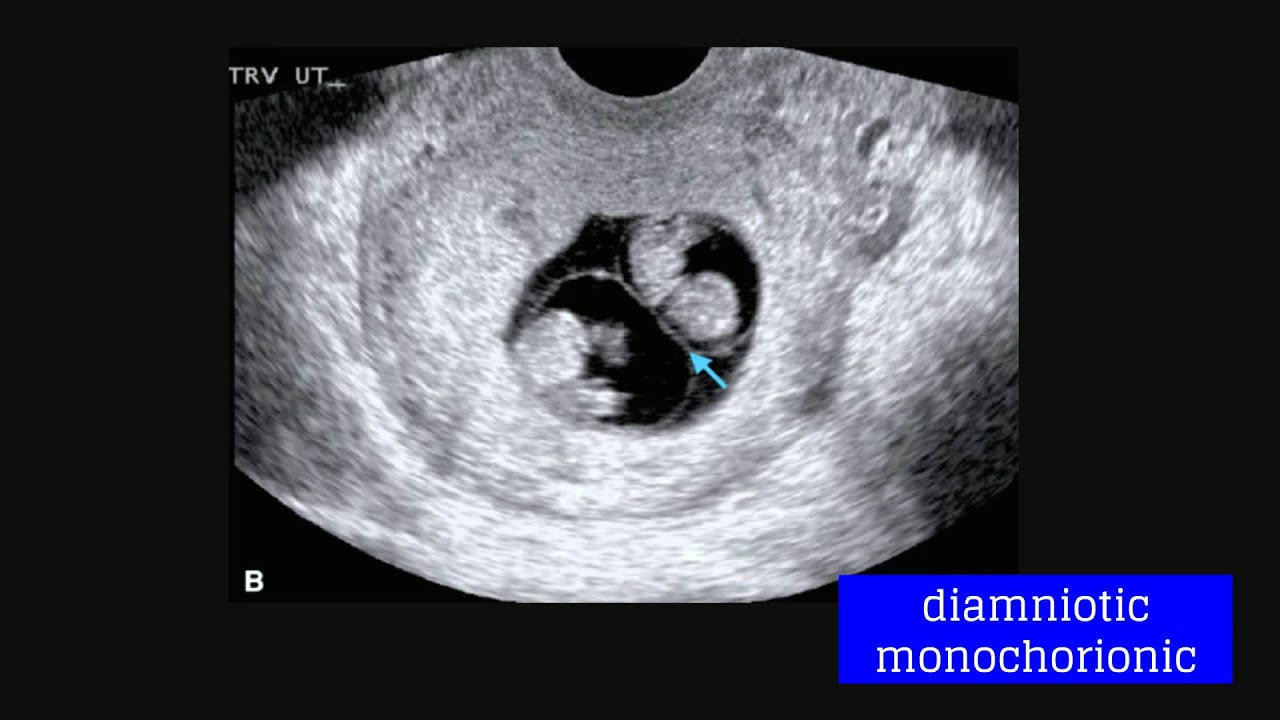

Summary Obgyn Multiple Gestation Royal College Of Surgeons Ireland A multiple gestation is considered a maternal health condition — a condition in the mother that may affect the baby or pregnancy. as exciting and joyful as a multiple birth is, it also increases the risk of such conditions as gestational diabetes, anemia, preeclampsia, and miscarriage. Screening, surveillance, and management strategies are delineated succinctly and organized by type of multiple gestation being managed from the lowest risk dichorionic twin pair to the increasingly escalating risks of twins and higher order multiples sharing a placenta and or amniotic sac. A comprehensive guide to understanding multiple pregnancies (twins, triplets, etc.), detailing the associated risks for mother and babies, methods of diagnosis, and crucial management strategies to ensure the healthiest possible outcomes. Find best ob gyns in los angeles, california & make an appointment online instantly! zocdoc helps you find ob gyns in los angeles and other locations with verified patient reviews and appointment availability that accept your insurance.

Multiple Gestation Obgyn Key At advanced perinatology, we provide expert maternal fetal care for all pregnancies, ensuring the best possible outcomes for both mother and baby. our team of board certified perinatologists offers cutting edge diagnostics, compassionate support, and personalized treatment plans. "the best ob gyn i've had to date! and i have a lot. she's got a terrific, outstanding bedside " more. At the fetal maternal center at children’s hospital los angeles, we provide care for complex fetal conditions. when routine tests show the possibility of a medical problem, pregnant women come to our program for diagnosis and treatment. Multifetal gestations have increased risks to the pregnant patient and the fetus and neonate, including gestational diabetes, preeclampsia, preterm delivery, growth restriction, postpartum hemorrhage, and stillbirth or neonatal death.

High Risk Pregnancy Ob Gyn In Nyc Maiden Lane Medical At the fetal maternal center at children’s hospital los angeles, we provide care for complex fetal conditions. when routine tests show the possibility of a medical problem, pregnant women come to our program for diagnosis and treatment. Multifetal gestations have increased risks to the pregnant patient and the fetus and neonate, including gestational diabetes, preeclampsia, preterm delivery, growth restriction, postpartum hemorrhage, and stillbirth or neonatal death.